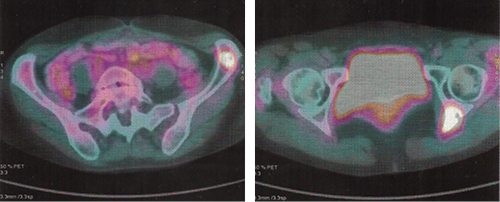

A los 12 meses de control por oncología, manifestó sensación de fatiga a los 30 minutos de ejercicio, así como presencia de tos predominantemente nocturna, por lo que se solicitó TAC de tórax, que fue reportada como normal, así como resonancia magnética de la zona quirúrgica; no se encontraron recidivas. En el control a los 17 meses postdiagnóstico, se encontró una baja de peso de cuatro kilogramos en un mes, por lo que se efectuó una tomografía por emisión de positrones (PET)/CT de cuerpo completo, la cual reportó la presencia de lesiones líticas en esqueleto axial y apendicular siguientes: extremo medial de clavícula derecha, apófisis transversa derecha de T8, hemicuerpo izquierdo de T9, apófisis transversa izquierda de L1, espina iliaca anterosuperior izquierda, acetábulo derecho, acetábulo izquierdo, isquion izquierdo, cuello quirúrgico de fémur derecho, además de nódulos pulmonares bilaterales (Figuras 3 y 4). Se catalogó en ese momento en estadio IVB. Actualmente es manejada de manera paliativa con ciclos de dacarbacina, gemcitabina, denosumab y factor estimulante de colonias de granulocitos, además de recibir radioterapia 30 Gy en 10 sesiones. Se encuentra (10-I-2015) en protocolo para realizar vertebroplastia o cifoplastia con metilmetacrilato con relación a manejo de dolor óseo; se anota que continúa realizando 30 minutos de ejercicio aeróbico diario.

Figura 3: Estudio PET/CT mostrando lesiones en esqueleto axial y apendicular con características líticas.